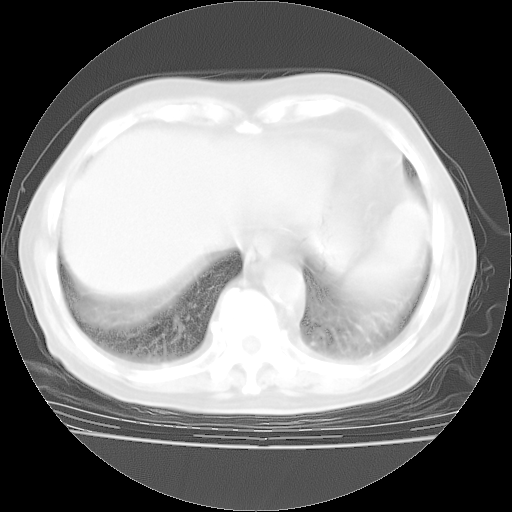

4月28日肺部CT——再次出现类似去年5月9日——透光度降低,“间质性”改变。

4月28日肺部CT——再次出现类似去年5月9日——磨玻璃样、间有“粟粒样”改变。

4月28日肺部CT

个人阅读4.14日肺部CT平扫:纵隔窗无异常,但肺窗示:双下肺内、后基底段有片絮状侵润影,部位以后基底段为著,以间质改变为主,呈急性肺泡炎征像,和首次住院影像学有相似之处。仅是个人读片,明日请相关专家再读片哈。其它建议同上。